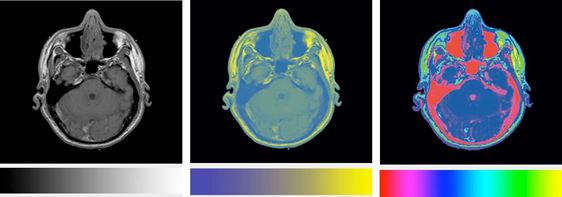

首先看一下下面这幅图:

是不是看到这个图的时候一副黑人问号脸?

这是什么?我是谁?我在哪里?这个图想表达什么?

3D图像提供的立体感会让我们大脑无法清晰的判断出表达的含义,线条的厚度产生的阴影等这些不必要的信息我们称之为图表垃圾,他们会干扰我们的大脑对于数据的判断。